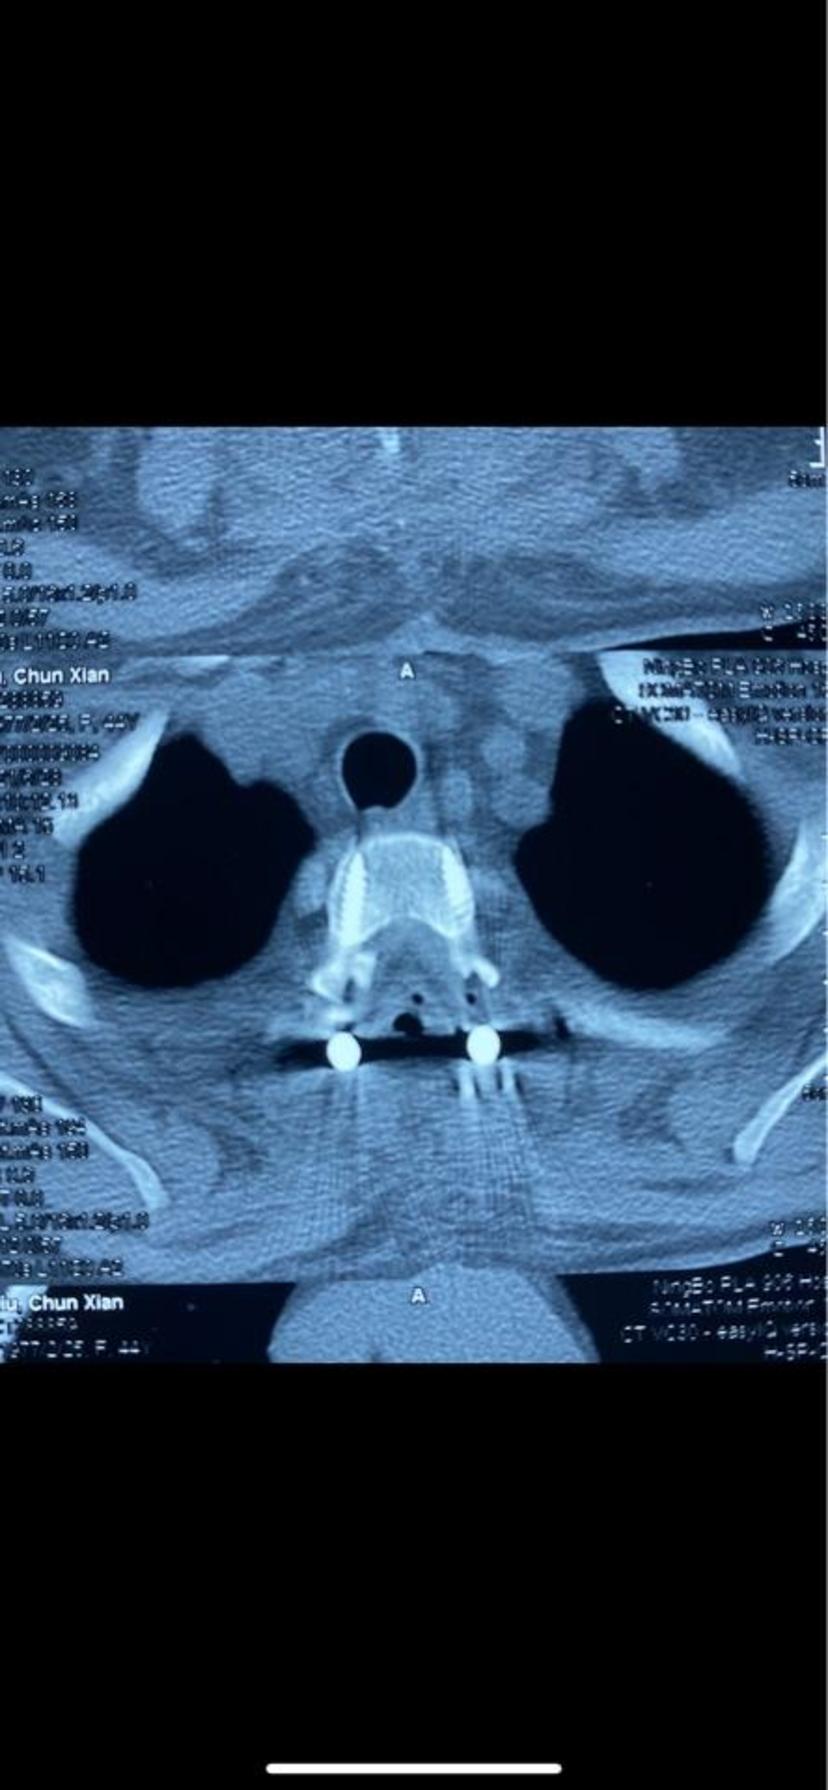

CT显示骨化物占满整个椎管,脊髓严重受压

CT平扫显示胸2-3平面黄韧带骨化占满